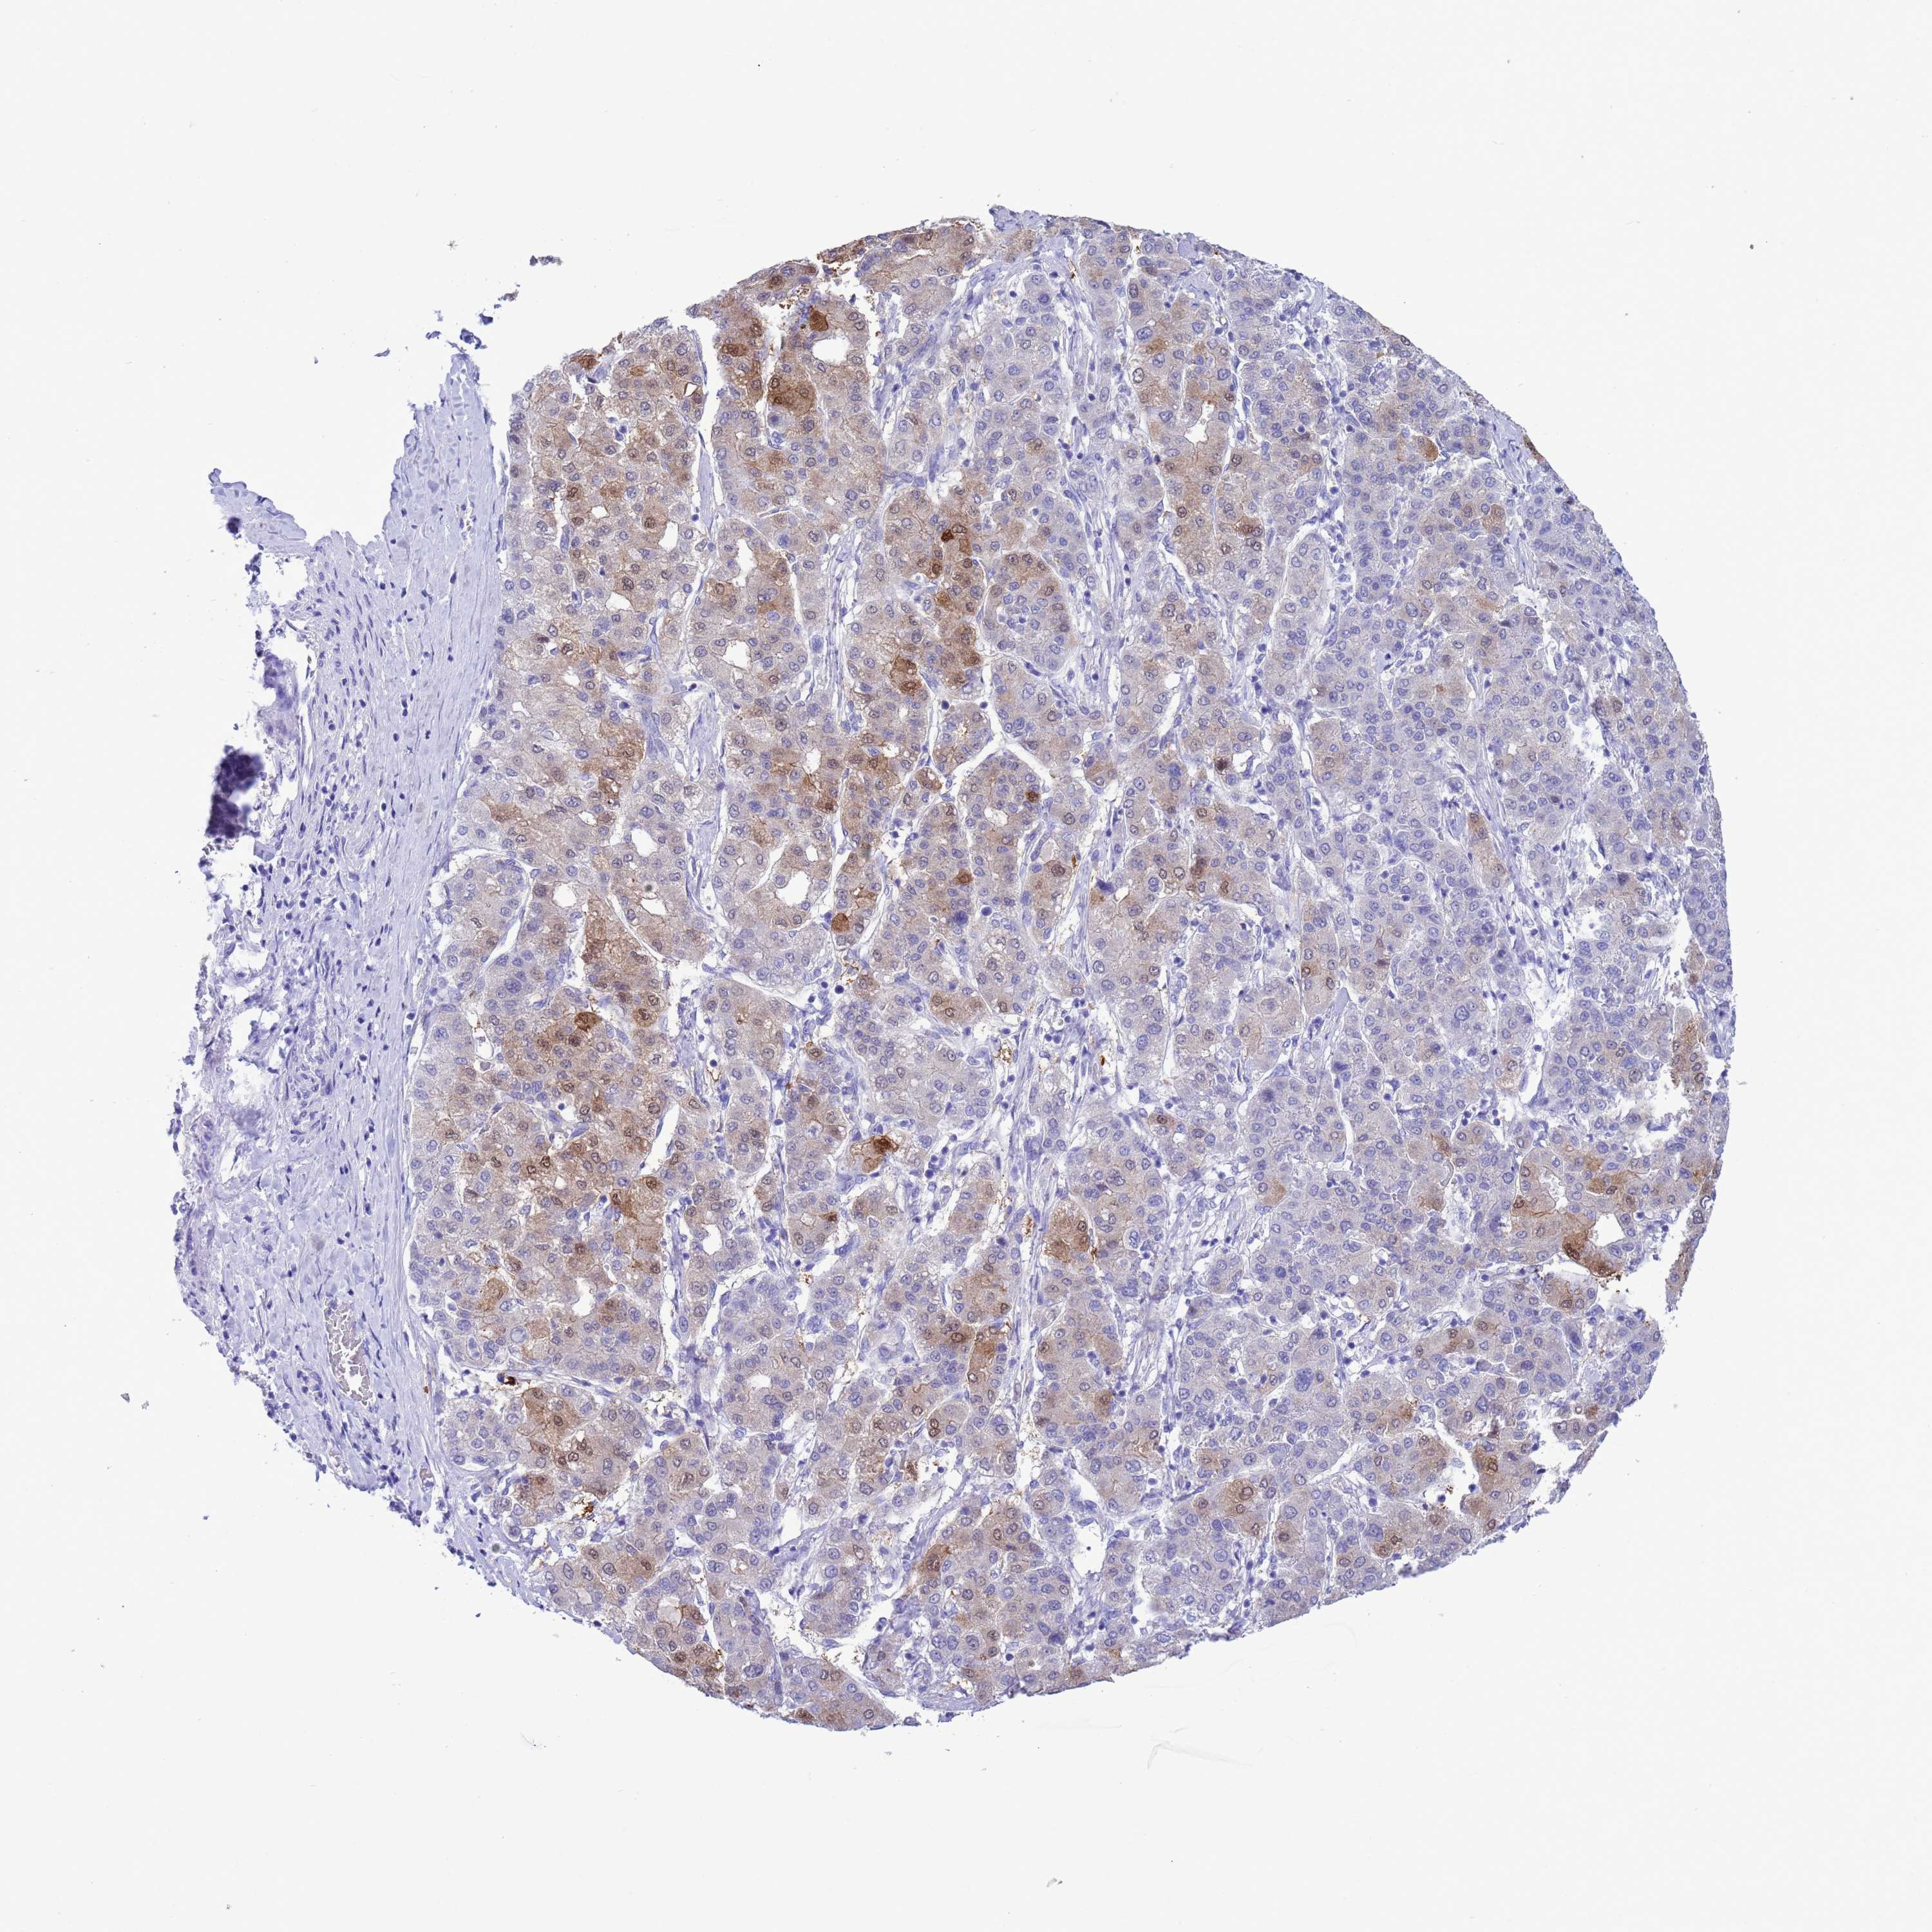

LIVER CANCER - Protein expressioni

A mouse-over function shows sample information and annotation data. Click on an image to view it in a full screen mode. Samples can be filtered based on level of antibody staining by selecting one or several of the following categories: high, medium, low and not detected. The assay and annotation is described here.

Note that samples used for immunohistochemistry by the Human Protein Atlas do not correspond to samples in the TCGA dataset.

Antibody stainingi

Antibody staining in the annotated cell types in the current human tissue is reported as not detected, low, medium, or high, based on conventional immunohistochemistry profiling in selected tissues. This score is based on the combination of the staining intensity and fraction of stained cells.

Each image is clickable and will lead to virtual microscopy that enables deeper exploration of all samples and also displays staining intensity scores, fraction scores and subcellular localization as well as patient and tissue information for each sample.

HPA048652

HPA055972

HPA055973

CAB022669

CAB047357

Cholangiocarcinoma

Carcinoma, Hepatocellular, NOS